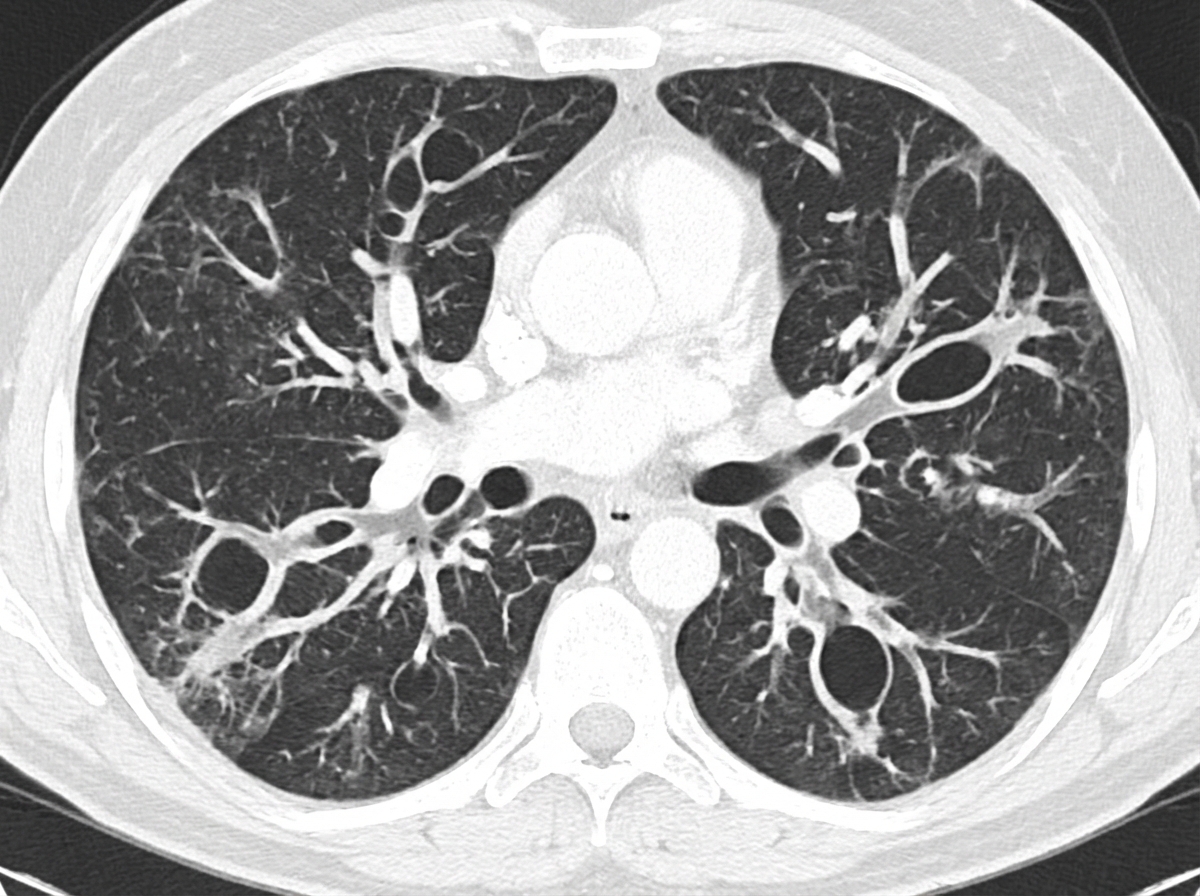

Lung transplantation candidacy US Medical PG Question 1: A 47-year-old man comes to the physician because of a 7-week history of cough, shortness of breath, and daily copious sputum production. He has had frequent respiratory tract infections over the past several years. Current medications include dextromethorphan and guaifenesin as needed. He does not smoke cigarettes. His temperature is 37.1°C (98.8°F), pulse is 88/min, respirations are 21/min, and blood pressure is 133/84 mm Hg. Pulse oximetry on room air shows an oxygen saturation of 95%. Diffuse crackles and wheezing are heard on auscultation over bilateral lung fields. A CT scan of the chest is shown. The patient is at greatest risk for which of the following complications?

- The patient's presentation with chronic cough, copious sputum, frequent infections, and diffuse crackles/wheezing, along with the CT scan findings suggestive of **bronchiectasis**, indicates severe and chronic airway inflammation and dilation.